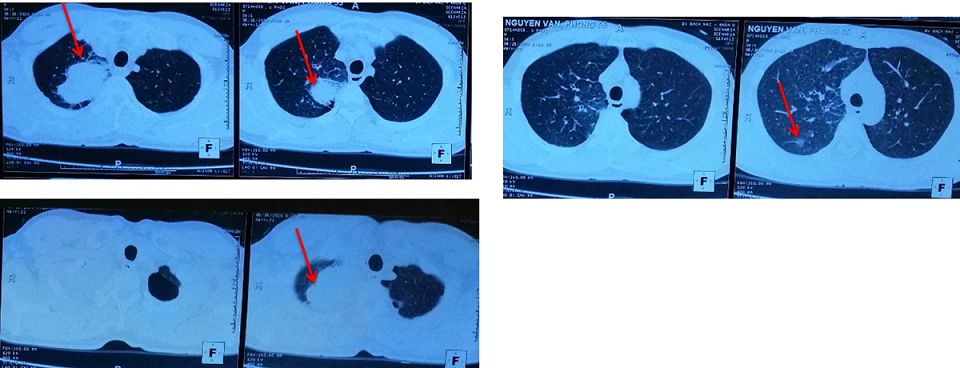

– Chụp cắt lớp vi tính lồng ngực:

Hình 1: Hình ảnh chụp cắt lớp vi tính lồng ngực: Hình ảnh khối u thùy trên phổi phải kích thước 5x6cm, hạch trung thất, rải rác tổn thương thứ phát hai phổi (Mũi tên màu đỏ).